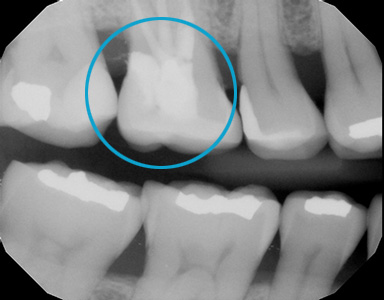

Ozone Treatment :

Bone healing with ozone treatment and SRP

Reverse Gum Disease: Bone Healing